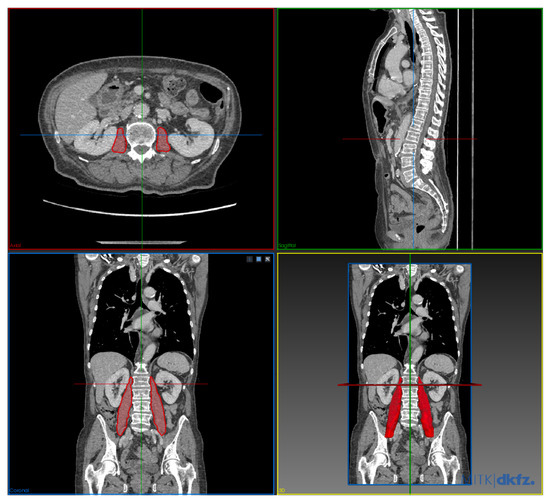

2.3. CT Body Composition Analysis

2.4. Statistical Analysis